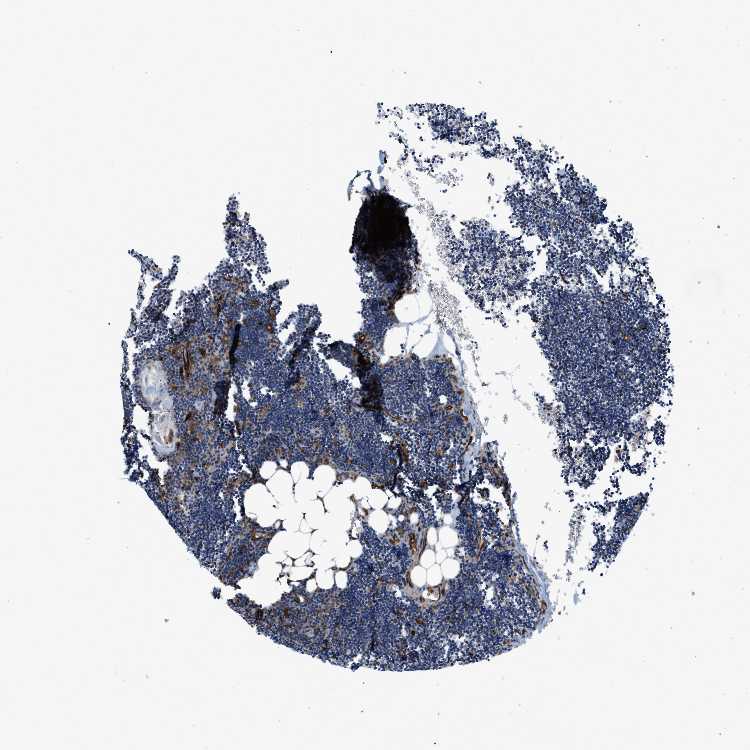

LYMPH NODE - Antibody stainingi

Antibody staining in the annotated cell types in the current human tissue is reported as not detected, low, medium, or high, based on conventional immunohistochemistry profiling in selected tissues. This score is based on the combination of the staining intensity and fraction of stained cells.

Each image is clickable and will lead to virtual microscopy that enables deeper exploration of all samples and also displays staining intensity scores, fraction scores and subcellular localization as well as patient and tissue information for each sample.

Antibody HPA013606Antibody HPA017964Antibody CAB015334Antibody CAB016402

Germinal center cells LowMediumLowMedium

Non-germinal center cells MediumHighMediumHigh